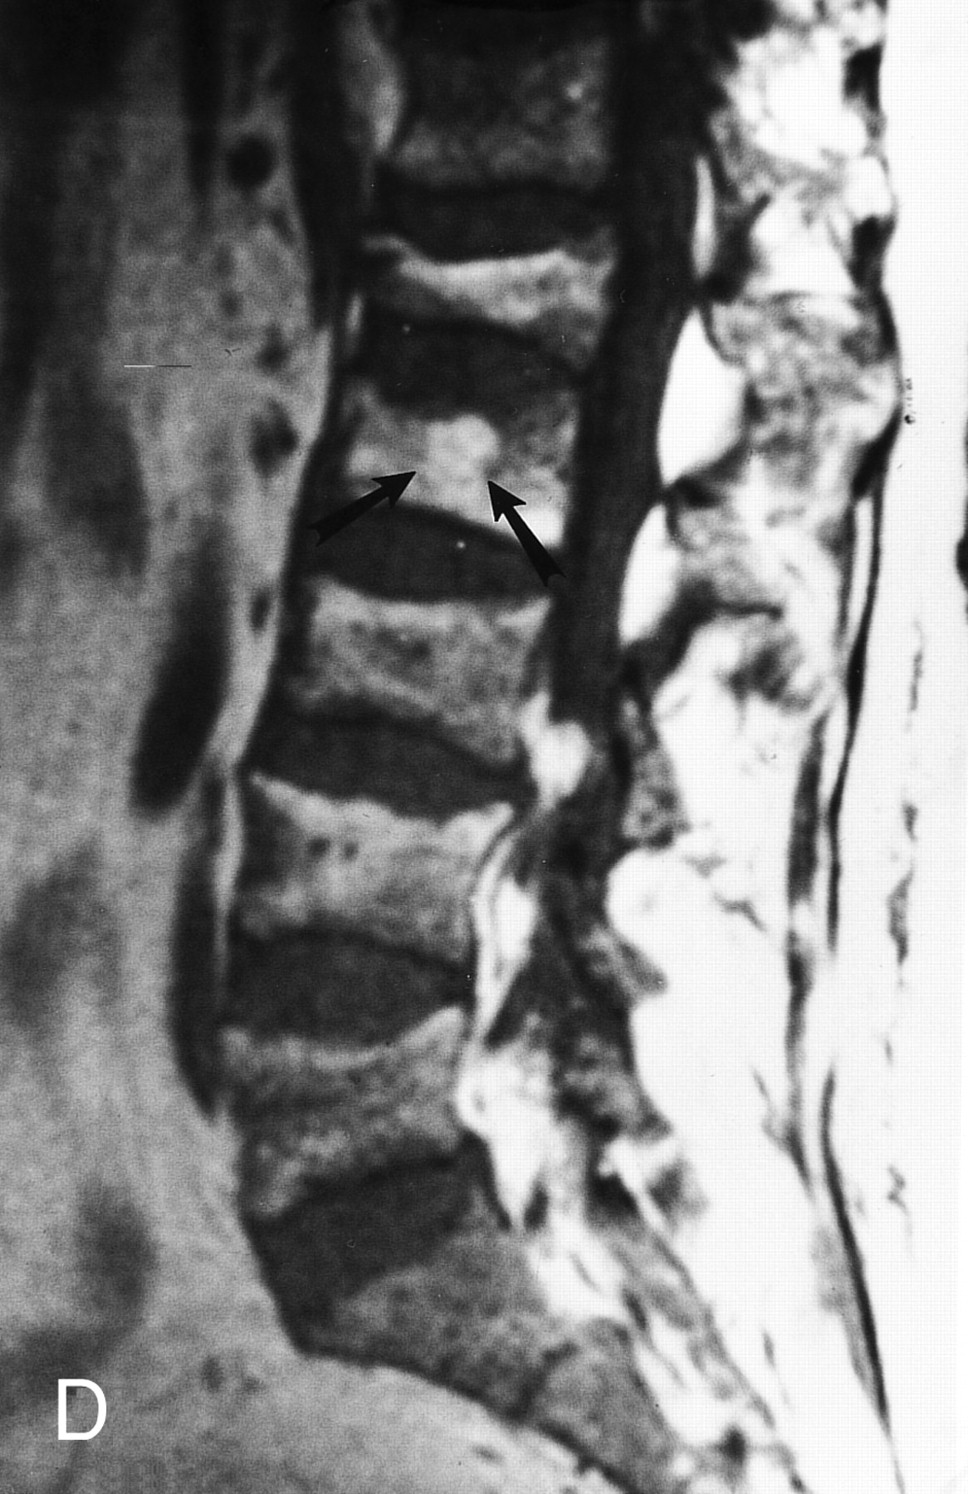

ГМ. СМ. Миеломная болезнь (множественная плазмоцитома). +

Миеломная болезнь (множественная плазмоцитома).

Лия А. Moulopoulos и Мелетий А. Dimopoulos